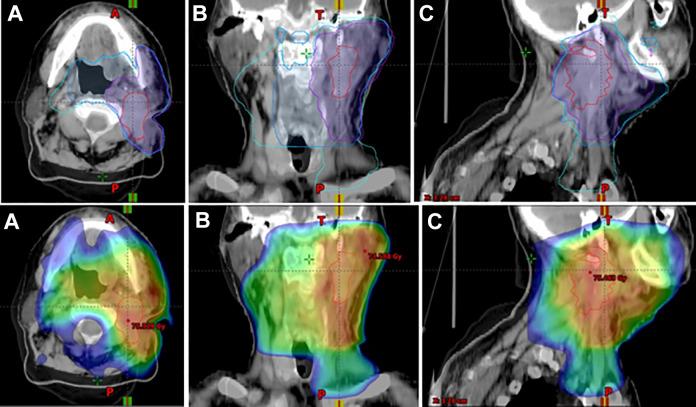

Eleven patients presenting a locoregional recurrence after head and neck carcinoma of unknown primary treatment with curative-intent radiochemotherapy performed between 2007 and 2017 in the departments of radiation oncology of 2 French cancer institutes. Images of the computed tomography scan or the magnetic resonance imaging performed at the time of the recurrence were fused with those of the simulation computed tomography scan to delimit a volume corresponding to the recurrence and to define the area of relapse compared to the volumes treated.

Irradiation was unilateral in 6 cases and bilateral in 5 cases. The median time to onset of recurrence was 7.24 months (extreme 3-67.7 months). Six patients had only a neck node recurrence, 3 had a neck node and subsequent primary recurrence, and 1 had only a median subsequent primary recurrence. Only 1 patient had synchronous distance progression to local recurrence. All neck node recurrences were solitary and ipsilateral. The subsequent primary recurrences were in the oropharynx in 3 cases and in the contralateral oral cavity in one case. All neck node recurrences were into the irradiated volume. The subsequent primary recurrences were either within or in border of the irradiated volumes. The median of the mean dose, received by neck node recurrences, was 69.9 Gy and that of the mean dose, minimum dose, maximum dose, and dose received by 95% of the volume of recurrence was 66.7 Gy. For the primary relapses, the median of the mean dose was 52.1 Gy and that of the mean dose, minimum dose, maximum dose, and dose received by 95% of the volume of recurrence was 39.9 Gy.

6 例为单侧照射,5 例为双侧照射。复发的中位时间为 7.24 个月(极端值为 3-67.7 个月)。6 例患者仅有颈部淋巴结复发,3 例患者有颈部淋巴结和随后的原发性复发,1 例仅有中位随后的原发性复发。仅有 1 例患者同时出现局部复发和远处转移。所有颈部淋巴结复发均为单发且同侧。随后的原发性复发分别发生在 3 例患者的口咽和 1 例患者的对侧口腔。所有颈部淋巴结复发均在照射体积内。随后的原发性复发位于照射体积内或边界内。颈部淋巴结复发的平均剂量为 69.9Gy,复发体积的平均剂量、最小剂量、最大剂量和 95%体积所接受的剂量分别为 66.7Gy。对于原发性复发,平均剂量为 52.1Gy,复发体积的平均剂量、最小剂量、最大剂量和 95%体积所接受的剂量分别为 39.9Gy。